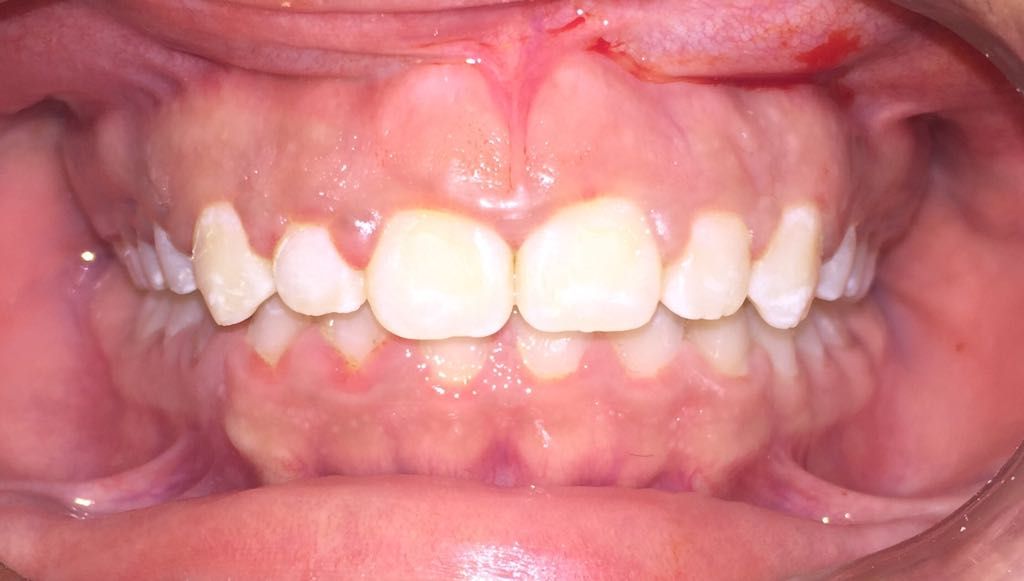

En la primera consulta se elabora un expediente clínico personalizado, respaldado por radiografías digitales y fotografías intraorales de alta precisión.

La realización de coronas dentales debe ser exclusivamente por un experto.La corona dental da protección y estética a un diente, no siempre requiere de tratamiento de endodoncia, solo en algunas ocasiones. El procedimiento requiere de mucha precisión para lograr una corona dental perfectamente bien sellada, de acuerdo a los mas recientes artículos científicos 8 de 10 coronas no sellan a la perfección.Anteriormente se realizaban coronas de metal con porcelana las cuales al cabo de un tiempo cambiaban de color y presentaban corrosión en el diente, en la actualidad contamos con diversos tipos de coronas realizadas por medio de CAD CAM zirconia, porcelana y otros materiales de alta calidad.

Diseño de sonrisa

Una alternativa inovadora para cambiar la forma y color de dientes es mediante el sistema U Venner de carillas de porcelana o de ceromero. Previamente se requiere de fotografías intraorales, toma de moldes dentales y toma de color dental. Excelente opción para diseñar una nueva sonrisa.